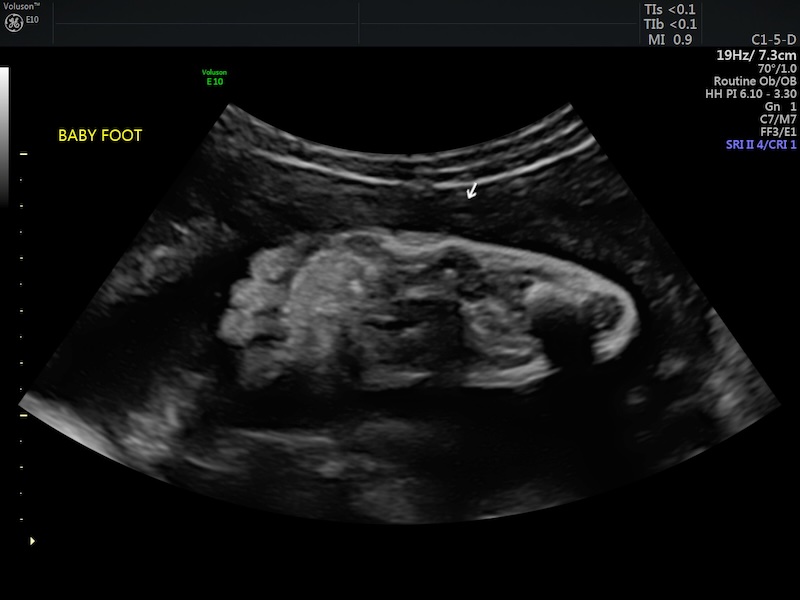

At 36 weeks and a few days, Jimmy and I headed to the hospital to have an ultrasound and appointment with maternal fetal medicine to check on baby’s growth and to go over options and such due to my gestational diabetes.